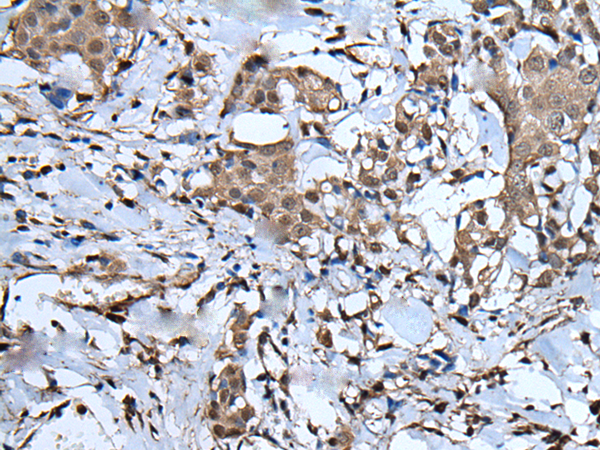

IHC positive control: |

Human liver cancer and human breast cancer |

IHC Recommend dilution: |

40-200 |